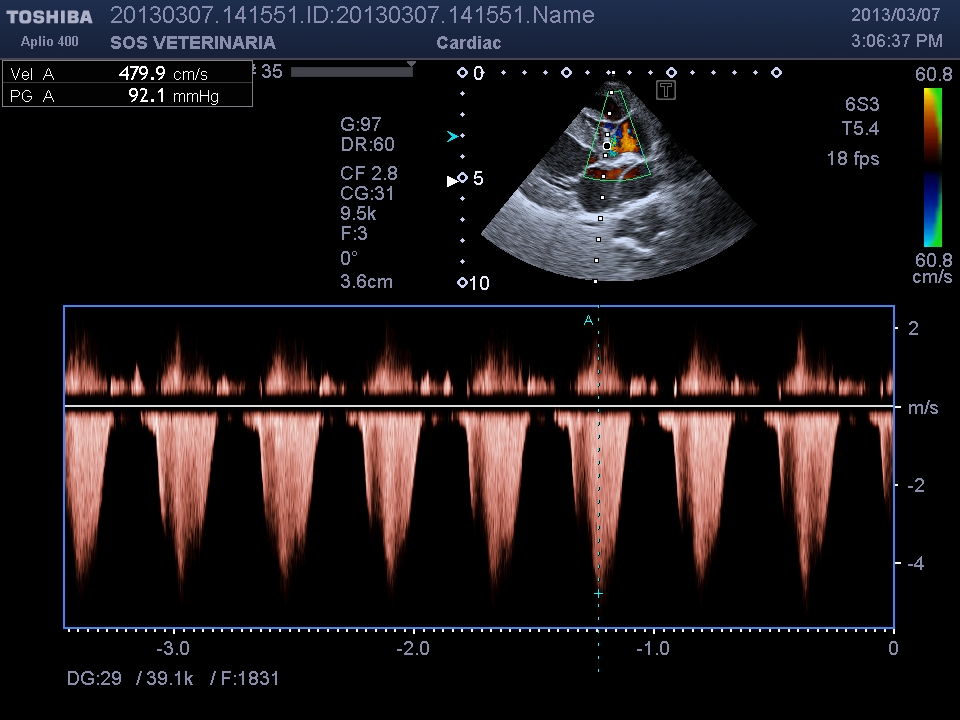

Ecco i filmati piu’ significativi osservare il flusso laminare che scorre parallelo alla parete laterale dell’arteria polmonare non piu’ continuo ma annullato in sistole dalla gittata in polmonare ,nel terzo filmato si vede l’ampolla del dotto

Quando si diagnostica un PDA il miglior momento di corregerlo chirurgicamente o con amplatzer e’ SUBITO. ovviamente dopo stabilizzazzione con diuretici se presenti sintomi . Aspettare porta il miocardio al rischio di sviluppare una insufficienza irreversibile,una volta invertito lo shunt ovviamente l’intervento e’ inutile rimane terapia medica per il controllo dell’ipertensione .(Sildefanil)